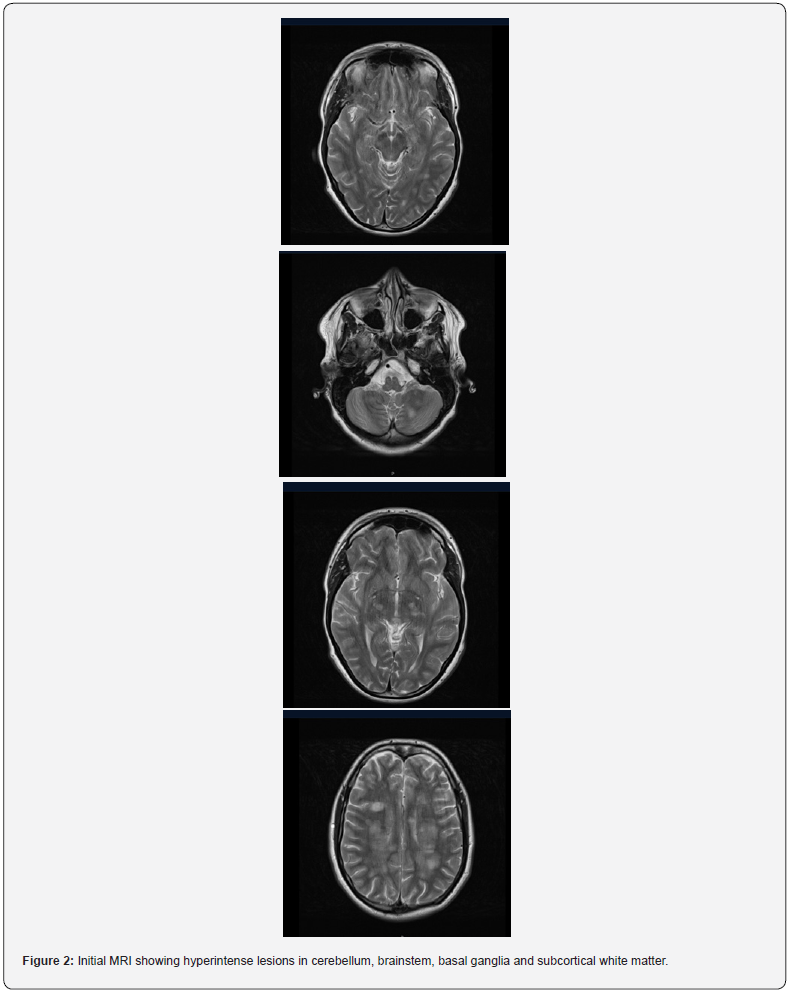

She was intubated for persistently low GCS and to facilitate an MRI. The MRI showed diffuse symmetrical T2/FLAIR hyperintensities involving deep and subcortical white matter, internal capsule, pons, cerebellum with diffusion restriction and enhancement, which was suggestive of acute disseminated encephalomyelitis (Figure 1). She was then started on pulse methylprednisolone. However, after 3 doses, she showed no signs of clinical improvement. Treatment was escalated to a 5-day course of intravenous immunoglobulin (IVIg). As she remained unresponsive, a tracheostomy was performed and transferred to our hospital for the possibility of plasma exchange.